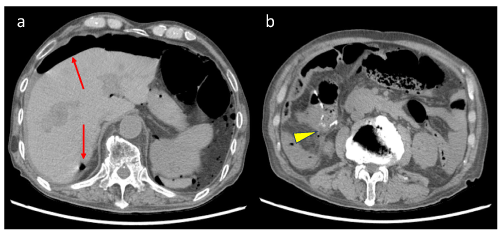

Figure 1. Contrast-enhanced computed tomography before surgery for primary colon cancer (A) Arrow: primary ascending colon cancer (B) Arrowhead: multiple liver metastases from colon cancer